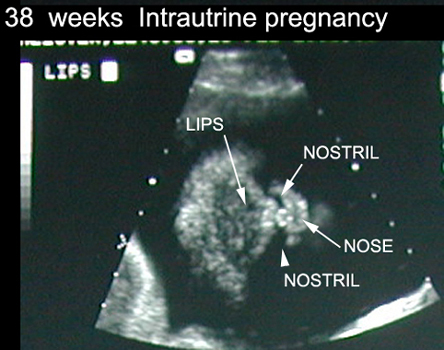

38 Weeks of Intrauterine Pregnancy |

|